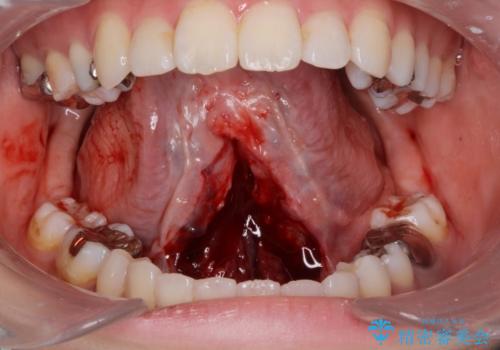

- 舌が動かしにくく、過去に舌小帯切除を行ったがあまり切除されず後戻りをしたため、舌小帯切除を希望されました。

舌小帯の形成術を行い、舌の可動域を広げました。